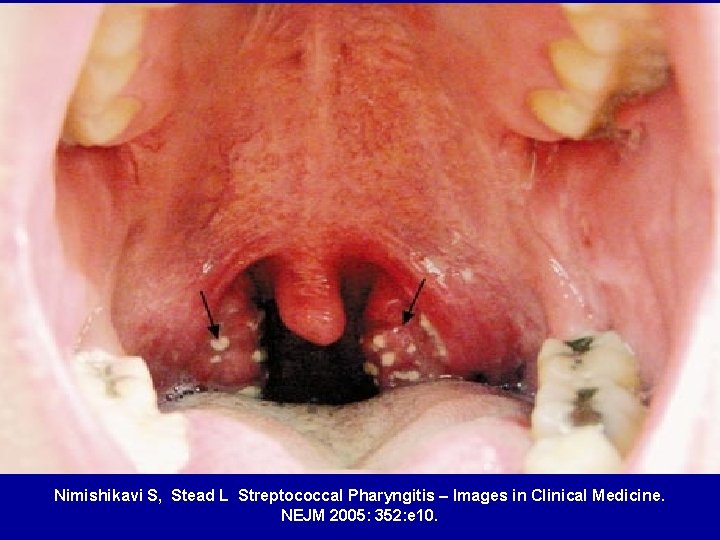

Nimishikavi S, Stead L Streptococcal Pharyngitis – Images in Clinical Medicine. NEJM 2005: 352: e 10.

Group A b-haemolytic streptococcus • All cases associated with recent infection (e. g. pharyngitis) • Antibody and cellular immune response crossreacts with human connective tissue

Rheumatic fever • Rheumatic fever is an inflammatory disease which may develop after a Group A Streptococcal infection such as: – Strep. throat infection or scarlet fever • Can involve the heart, joints, skin, and brain • It commonly appears in children ages 5 through 15